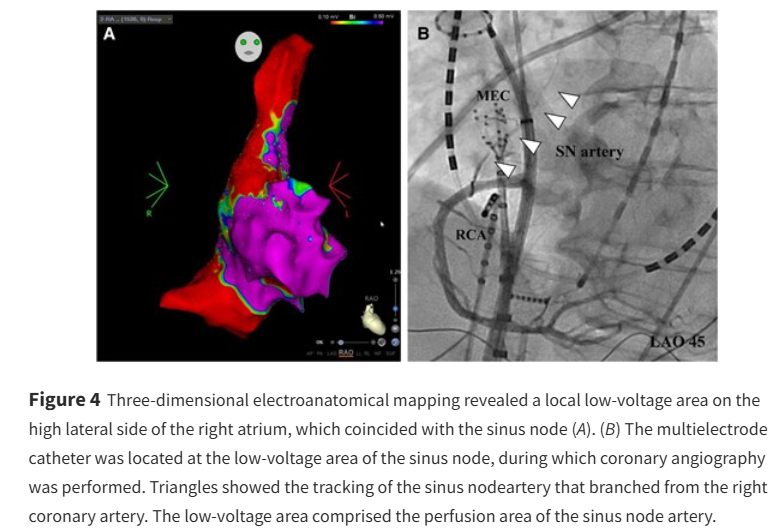

A non-idiopathic case of sick sinus syndrome ow.ly/zlJJ50VSnfE #EHJCaseReports Philipp Sommer Tee Joo YEO Aaysha Cader Boldizsar Kovacs Erik Rafflenbeul A.Nazmi Calik Obayda Azizy Sara Moscatelli EHJCaseReports Editor-in-Chief #CardioX #EPeeps